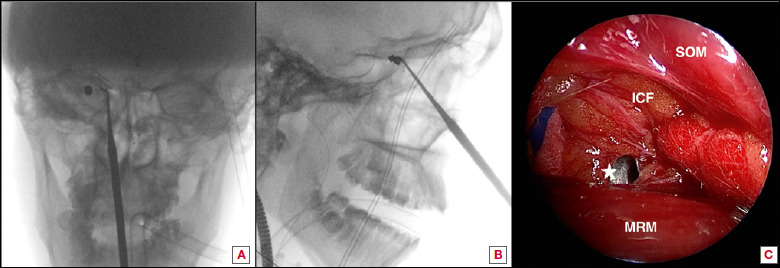

简介眶内异物(IOFB)是一项临床挑战:手术治疗可能会引起争议,并提出了不同的策略。在建议取出异物时,根据异物的位置和性质,人们提出了外部和内窥镜两种方法,但进入眼眶的手术通道和发病率却大不相同:方法:我们对接受内窥镜经鼻手术治疗的 IOFB 病例进行了文献回顾,以评估这种手术在这些病例中的作用。我们还介绍了一例采用内窥镜经鼻方法成功取出眶内子弹的病例,该病例在眼球运动和视力方面取得了良好的效果:结果:采用内窥镜经鼻方法治疗的眶内子弹数量有限。在内侧区,这种方法似乎安全有效。在我们的病例中,患者在术后两个月完全康复,没有明显的长期后遗症:在可行的情况下,经鼻内窥镜方法治疗眶内异物是一种有效的手术技术,可获得最佳疗效和令人满意的恢复。

Methods: We performed a literature review of cases of IOFBs that received exclusive endoscopic transnasal surgical treatment to evaluate the role of this surgery in these occurrences. We also present a case of an intraorbital intraconal bullet that was successfully removed using an endoscopic transnasal approach with good outcomes in terms of ocular motility and visual acuity.

Results: A limited number of cases of IOFBs have been treated with an exclusive endoscopic transnasal approach. When in the medial compartment, this approach appears to be safe and effective. In our case, two months after surgery the patient showed complete recovery with no significant long-term sequelae.